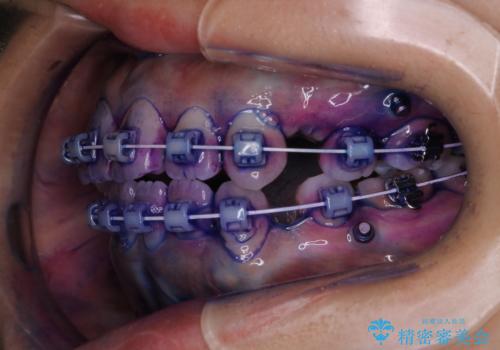

毎日しっかりと磨いているようでも、装置の周りや歯と歯の間・歯と歯茎の間に磨き残しが残ってしまいます。そのため磨き残しをチェックする『染め出し剤』を使用すると明確に磨き残しを見ることができます。

染め出されている部分の磨き残しは、毎日の習慣として歯ブラシをしていてもいつも磨けてない部分です。

この部分をしっかりと磨けるようになると、虫歯や歯周病を予防することができます。

矯正中にも、虫歯や歯周病予防をしっかり行うことが大切です。